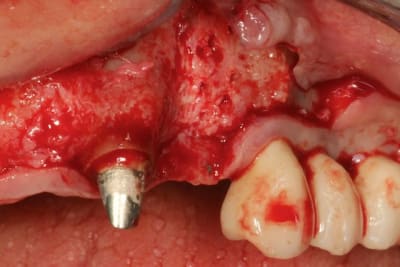

Grosse perte osseuse au niveau de la 23, ROG avec Bio-Oss et autogène dans un rapport 50/50, le tout recouvert pas une BIo-gide maintenu avec de pin's.

Désolé pour le retard, je vais essayé de répondre à tout le monde, mettre un implant et faire une ROG de façon predictible dans un cas comme ça c'est impossible, la photo pré-op c'est la dernière ( je ne sais pas pourquoi nonol m'a inversé l'ordre ), à noter que j'ai fait ce design d'incision car 24 et 25 sont des implants et je ne voulais justement pas me retrouver avec une récession.

J'ai utilisé du BIo-Oss et de l'autogène prélevé avec un scraper à la mandibule, le tout recouvert par une Bio-Gide maintenu par des pin's, suture avec du Gore Tex ( e-PTFE ) et du Cytoplast (PTFE )